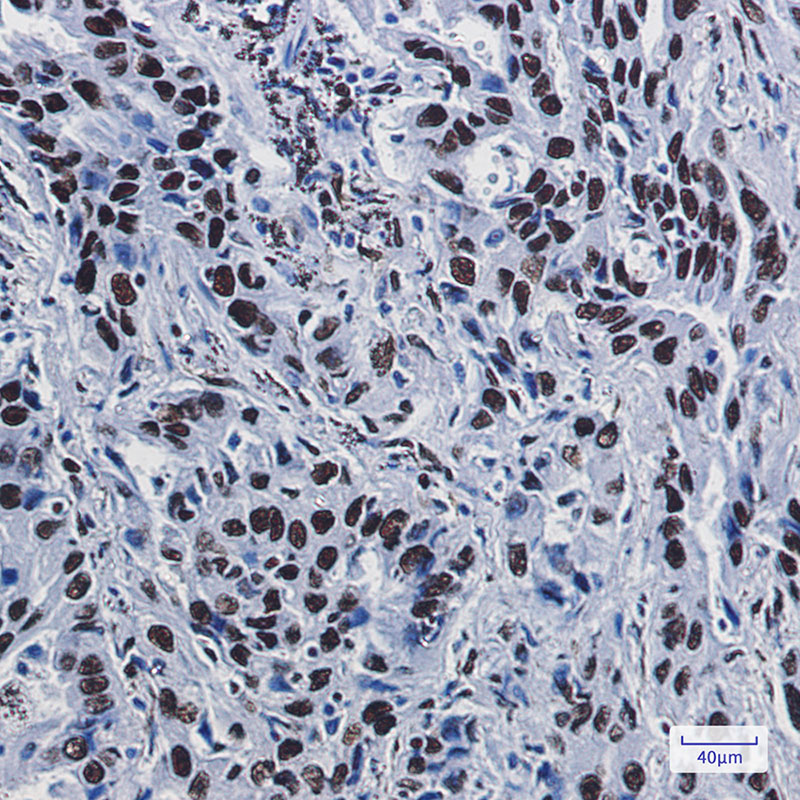

IHC 1/50-1/100 Human,Mouse,Rat

**摘要**:报道了一种新型抗人ILF3的小鼠单克隆抗体的制备与验证。该抗体(克隆号:3B5)在ELISA、免疫组化中表现出高特异性,并成功应用于肺癌组织样本中ILF3蛋白过表达的检测,提示其作为预后标志物的潜力。